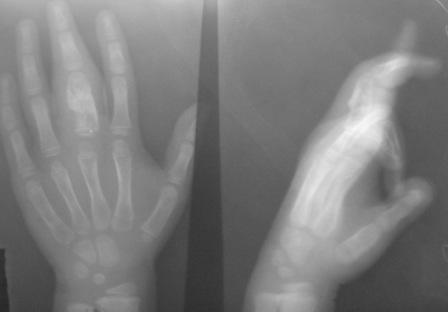

Уважаемые коллеги, на осмотре девочка 2006 г.рожд.

Со слов матери 3мес. назад заметила припухлость основного фаланга 3-пальца, которая постепенно увеличилось до настоящего размера где-то в течении месяца, не болит, ребенка не беспокоит, признаки воспаления отсутствуют. Консультация онколога, биопсия - опухоль исключена (со слов матери), фтизиоортопед - тбс исключен. От основной фаланги 3 пальца к головке 4-пястной кости под кожей прощупывается хрящевидная ткань.

Р-граммы от 10 декабря и 15 февраля, и фото прилагается.